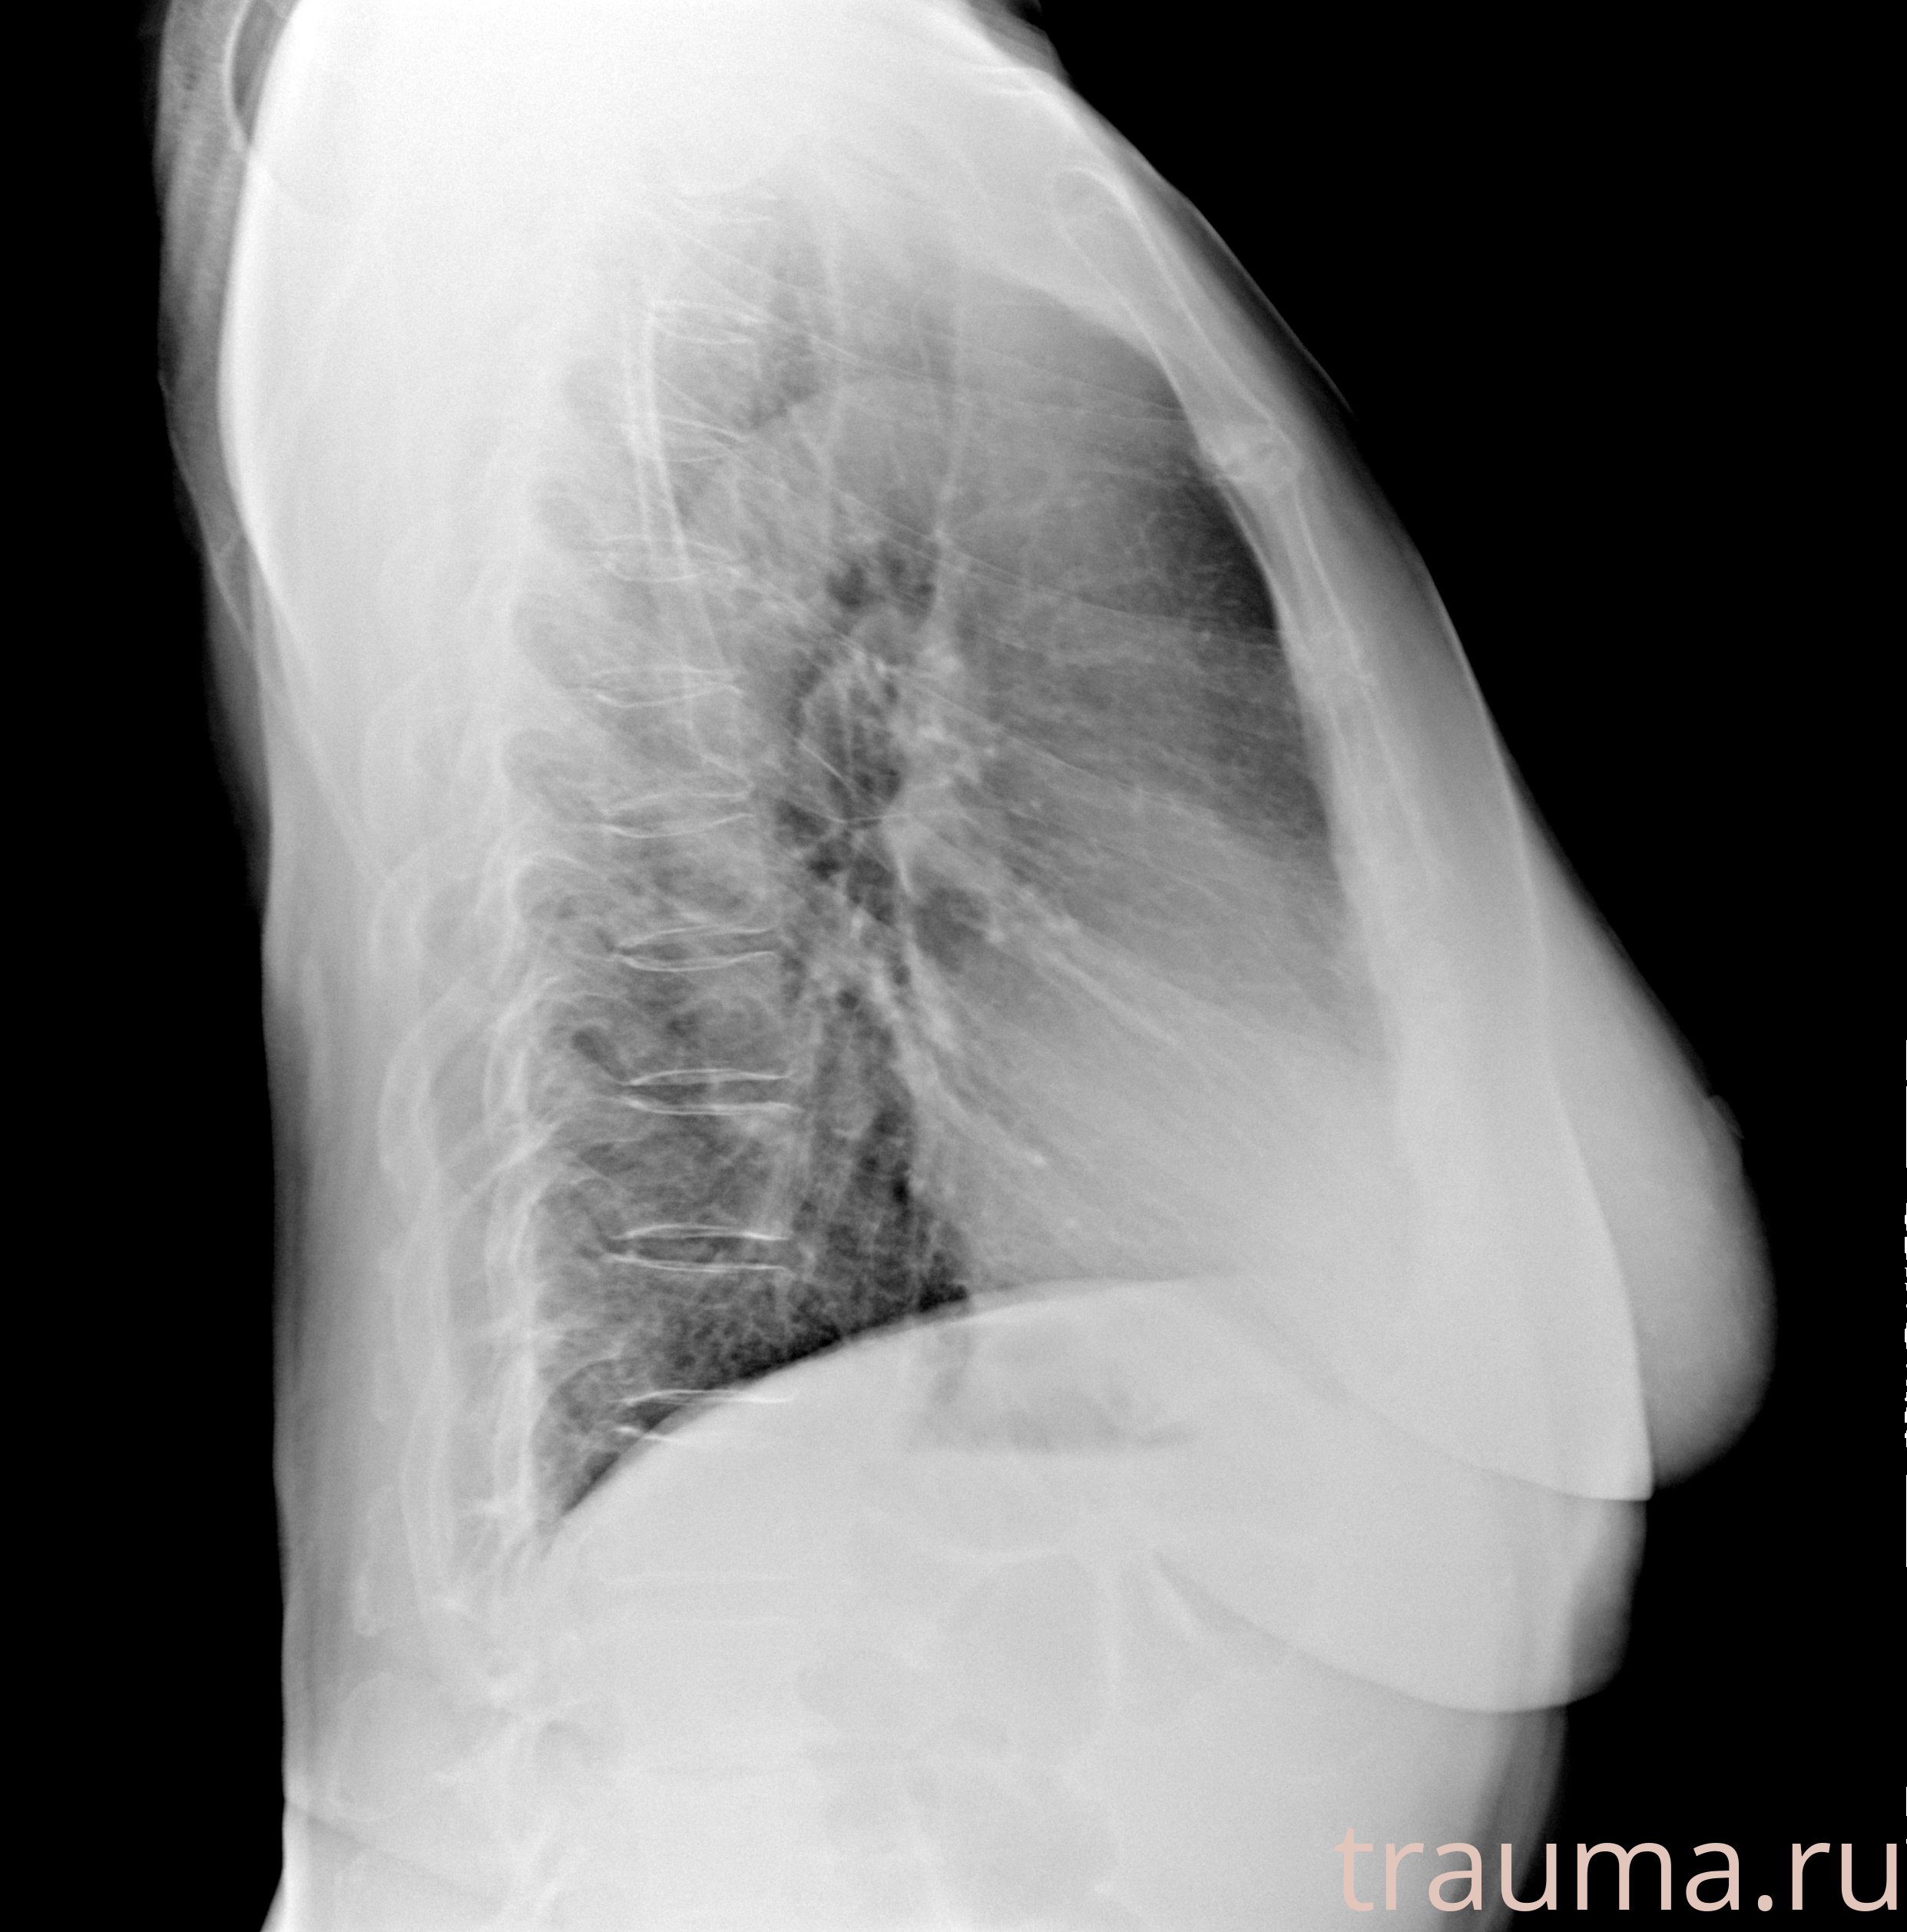

Рентгенограммы

Рентген на дому: по вашему адресу приезжает врач-рентгенолог, травматолог-ортопед с мобильным рентгеновским аппаратом, проводит диагностику травмы или заболевания, делает необходимые рентгенограммы, дает рекомендации по дальнейшему лечению. Получить качественные снимки в домашних условиях возможно благодаря уникальной методике, разработанной МосРентген Центром для института  Склифосовского

при переломе шейки бедра и пневмонии от компании МосРентген Центр - партнера Института имени Склифосовского